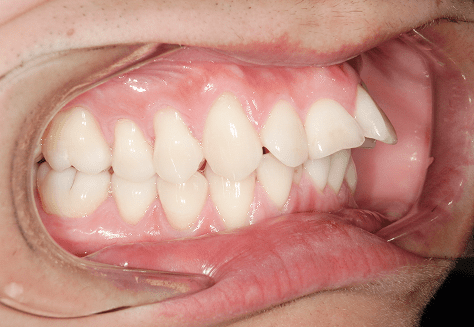

S.K

治療前

治療後

主訴

歯が重なっていて気になる。前歯が出ていて唇が閉じにくい。ハミガキがしにくい。

診断

上顎前突・叢生

年齢/性別

20代/男性

抜歯部位

上下第三大臼歯

使用装置

上下インビザライン

保定装置

上下ビベラリテーナー

診察料金

1,100円×33回

治療期間

3年5カ月